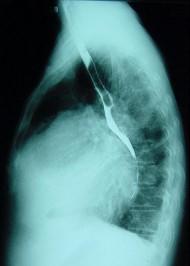

对如下心脏左侧位片描述正确的是 ( )A、正常心脏B、以上均错C、左心房Ⅰ度增大D、左心房Ⅲ度增大E、右心房增大

选项 A、正常心脏 B、以上均错 C、左心房Ⅰ度增大 D、左心房Ⅲ度增大 E、右心房增大

答案 D